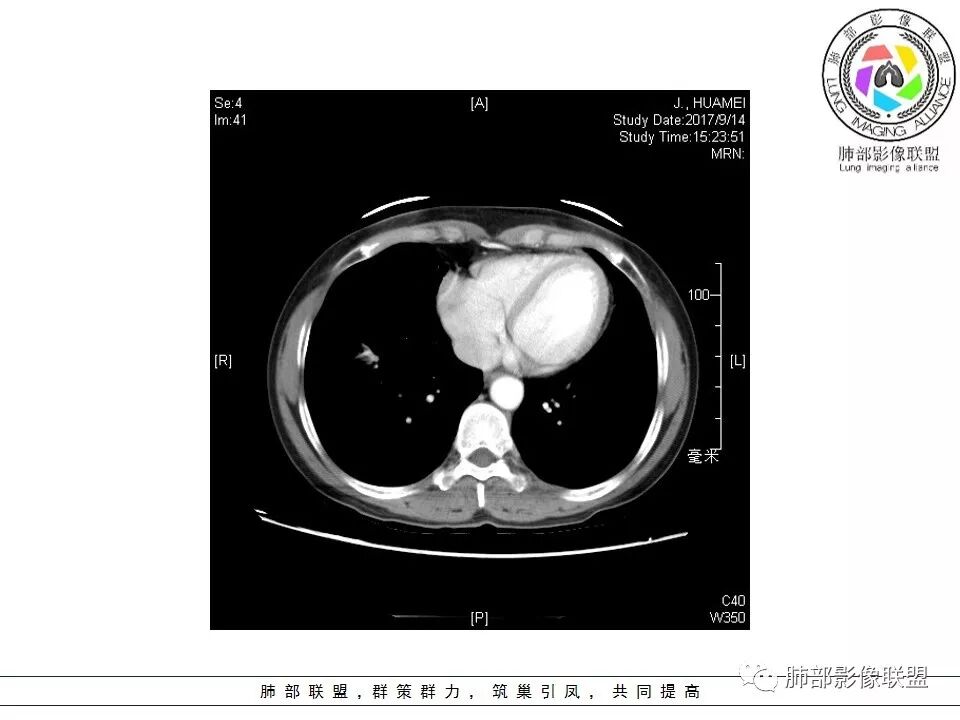

胸CT:右肺下叶前基底段占位性病变,内可见支气管穿过,病灶边缘不规则,呈浅分叶,未见明显毛刺。纵隔窗可见病灶密度相对均匀,增强可见病灶强化,内可见血管增粗,边缘模糊,总体考虑恶性,腺?。良性疾病鉴别错构。

恶性的血管穿行自然,包括支气管稍扩张,最常见还是淋巴瘤,它强化比较均匀;

粘液腺癌一般支气管扩张比较罕见,这个密度及强化太均匀,不是很符合,所以把淋巴瘤放前面,癌待排;

病灶的密度:密度均匀,部分病灶内可见空洞及气液平,轻中度均匀强化

血管造影征:肿瘤组织浸润引起间质增厚、肺泡壁破坏、肺泡腔充填,而周围充盈血管走行自然,未受肿瘤侵犯。

MALT淋巴瘤为低度恶性肿瘤,是肺内原发性淋巴瘤中最常见的类型,其部分征象与其他肺内恶性淋巴瘤表现不一样;因为MALT淋巴瘤生长缓慢,对缺氧耐受好,病灶中罕见坏死。很少引起胸内淋巴结,肺门及纵膈内淋巴结一般不肿大。胸膜及叶间裂轻度累及或不累及,胸膜增厚少见,胸膜外脂肪间隙清晰,即使累及胸膜,引起胸腔积液也少见,如有胸腔积液也多为良性,与淋巴管或静脉阻塞有关,也可能为病变靠近胸膜而发生的反应性渗出。肺MALT淋巴瘤具有一定的散播性,就诊时40%以上的病人存在肺外器官受累,最常见的肺外器官受累是胃。